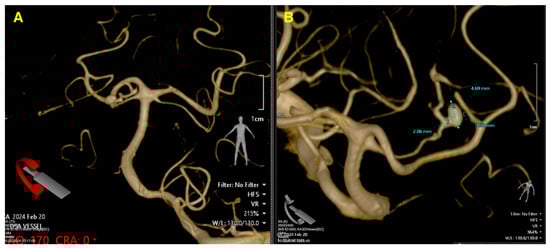

The postoperative CT scan (Figure 3) confirms a successful outcome following the aneurysm clipping procedure. The images demonstrate that the Yasargil clip is securely positioned at the neck of the aneurysm on the left superior cerebellar artery, with no evidence of compression or compromise to the parent vessel. The surrounding brain tissue shows no signs of new hemorrhage or ischemic changes, and the previously noted cerebellar collapse has remained stable without progression. Ventricular size is within normal limits, with no signs of hydrocephalus or cerebrospinal fluid obstruction. Additionally, the bone flap is well-fixed, with no complications related to the craniotomy site. The absence of postoperative complications, such as rebleeding or infarction, alongside the stable positioning of the clip, indicates a smooth recovery process. Clinically, the patient has shown significant improvement, with a marked recovery of consciousness and resolution of preoperative symptoms, such as somnolence and meningeal irritation. The absence of complications, such as rebleeding or ischemia, combined with the secure positioning of the clip and the stable postoperative neurological examination, supports the conclusion of a highly successful intervention.

Figure 3. Post-op control CT scan. The axial view (A) clearly demonstrates the secure placement of the Yasargil clip at the neck of the aneurysm, with no evidence of residual aneurysmal filling or new hemorrhagic events. The surrounding brain parenchyma shows no signs of ischemic damage, indicating effective hemostasis and preservation of cerebral perfusion. The bone window in the axial plane (B) confirms the intact positioning of the occipital bone flap, which was secured with Craniofix, with no evidence of complications, such as fractures, dislodgement, or hematoma formation, at the craniotomy site. The coronal view (C) highlights the absence of midline shift, ventricular enlargement, or hydrocephalus, reflecting stable intracranial pressure and normal cerebrospinal fluid dynamics. The cerebellar and brainstem structures appear anatomically intact and unaffected by the surgical intervention. The sagittal reconstruction (D) further confirms the precise placement of the clip and the complete exclusion of the aneurysm, with no evidence of residual filling or recurrence. Additionally, there are no signs of mass effect or compression on adjacent structures.